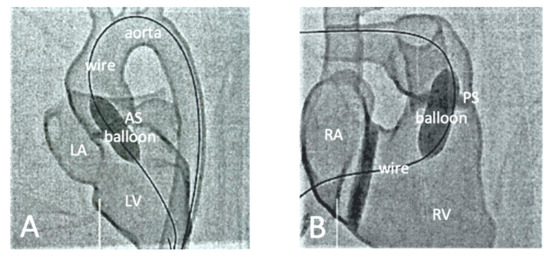

- Wu, C.-A.; Squelch, A.; Jansen, S.; Sun, Z. Optimization of computed tomography angiography protocols for follow-up type B aortic dissection patients by using 3D printed model. Appl. Sci. 2021, 11, 6844. [Google Scholar] [CrossRef]

- Wu, C.-A.; Squelch, A.; Sun, Z. Investigation of Three-dimensional Printing Materials for Printing Aorta Model Replicating Type B Aortic Dissection. Curr. Med. Imaging Rev. 2021, 17, 843–849. [Google Scholar] [CrossRef]

- Wu, C.-A.; Squelch, A.; Sun, Z. Assessment of optimization of computed tomography angiography protocols for follow-up type B aortic dissection patients by using a 3D-printed model. J. 3D Print. Med. 2022, 6, 117–127. [Google Scholar] [CrossRef]